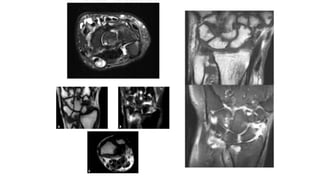

ARTRITIS REUMATOIDES

• La artritis reumatoide es una forma de artritis que causa dolor, inflamación,

SÍNTOMAS

Además de la inflamación de las articulaciones, la artritis

reumatoide presenta otros síntomas que pueden indicar

que es momento de realizarse una resonancia magnética:

• Dolor de articulaciones en pies, manos y rodillas

• Fiebre

• Pérdida de funciones en las articulaciones

• Articulaciones rígidas

• Fatiga

• Enrojecimiento de articulaciones

• Nódulos reumatoides

• Calor en las articulaciones

• Deformidad en las articulaciones

DIAGNÓSTICO

• Un diagnóstico de artritis reumatoide suele involucrar

un examen físico, un análisis sanguíneo que detecte la

presencia del “factor reumatoide” y una resonancia

magnética que permita visualizar con más claridad el

daño causado por la enfermedad.

TENDINITIS